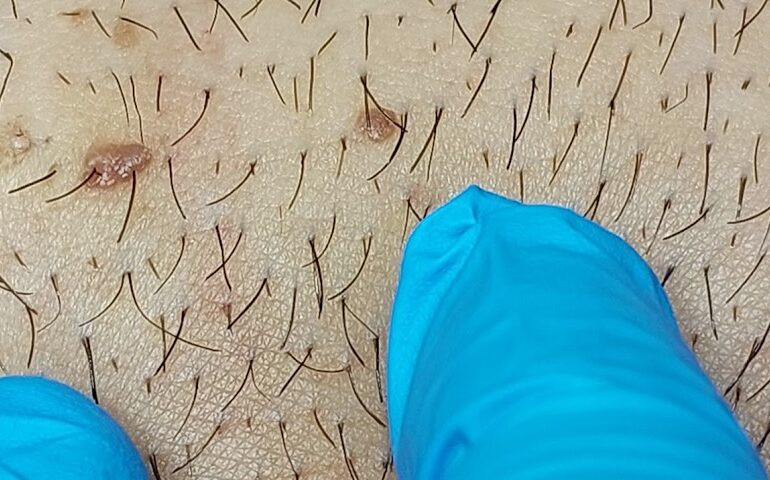

HPV